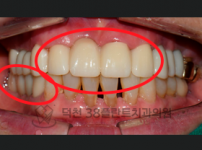

치료전후